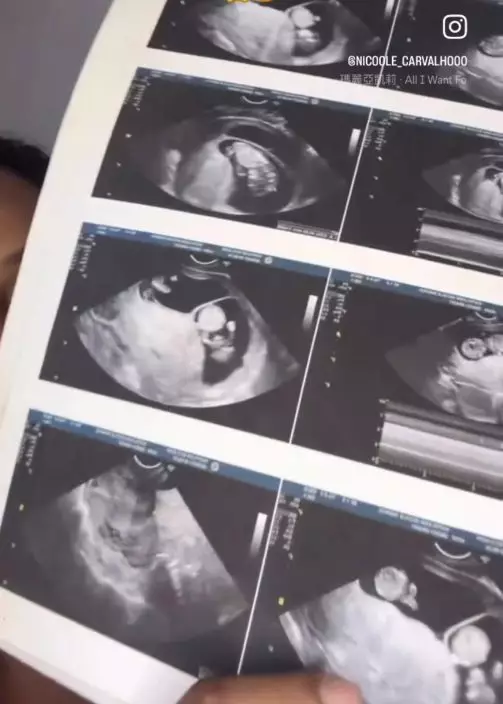

超聲波證兩胎相差一周 列為高風險妊娠需臥床

凱瑟琳之後接受超聲波檢查,結果證實腹中懷有兩名胎兒,且兩者胎齡相差約1周。由於情況罕見且風險較高,醫生隨即列為高風險妊娠個案,並建議她盡量臥床休息。